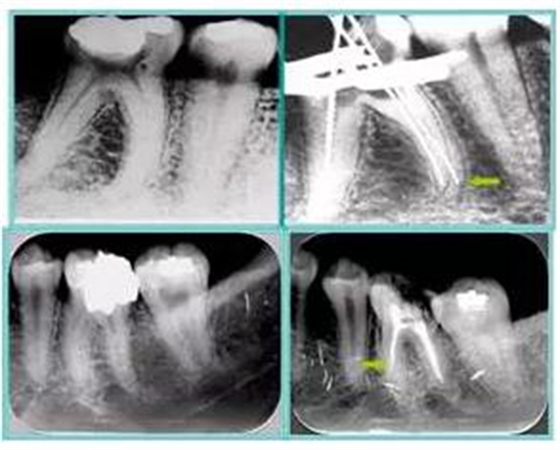

左圖和上圖為干髓治療后牙齒,齲齒疏通后進(jìn)行根管充填。

如圖為塑化加根充處理后牙齒 X 線(xiàn)片。

注意:沒(méi)有病變,叩疼陰性,沒(méi)有陽(yáng)性體征,X 線(xiàn)片示不理想的根管治療狀態(tài),根尖沒(méi)有異常,根周膜影像正常時(shí),表明療效較好,不要強(qiáng)行治療。文獻(xiàn)報(bào)道根管治療再治療成功率 50% ,進(jìn)行再次治療應(yīng)慎重。